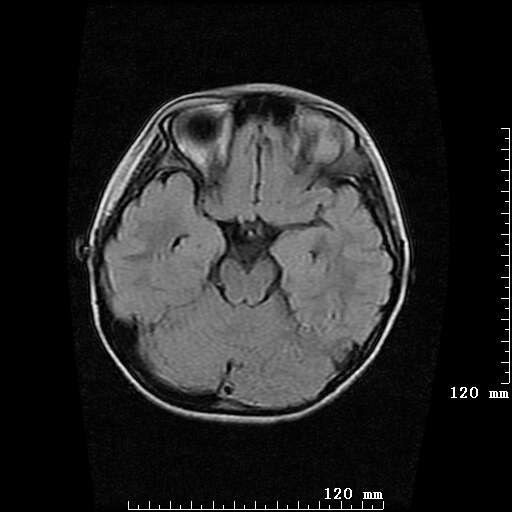

女,7岁,三岁才说话、走路。现智力尚可,走路不稳。临床怀疑大脑发育不全。

脑折质变薄,双侧侧脑室稍扩张,支持考虑脑折质发育不良

侧脑室周围白质软化症。

考虑胼胝体发育不全,髓鞘形成不良。

支持考虑胼胝体发育不全,髓鞘形成不良。

脑裂畸形伴灰质异位

侧脑室周围白质数量减少,侧脑室不对称性扩大,左侧侧脑室后角呈方形改变,脑沟加深,结合临床考虑脑室周围白质软化症(pvl)。期待结果!

只看出灰质异位

支持脑白质发育不良。